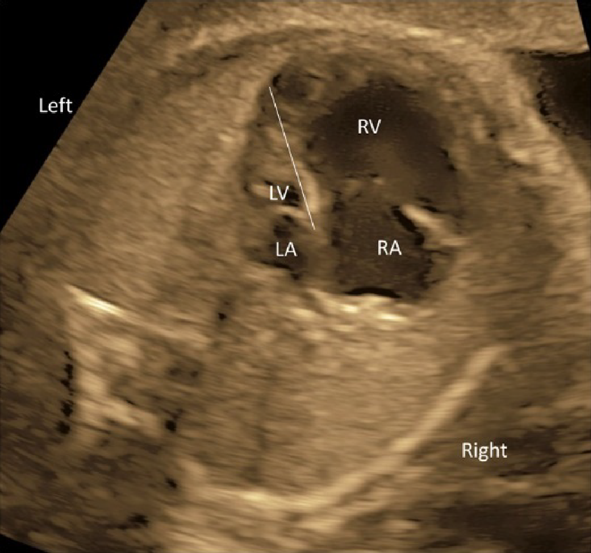

(2) 4CV

- The laterality of the left and the right ventricles can be determined using the 4CV. The right ventricle is characterized by the moderator bands within its cavity.